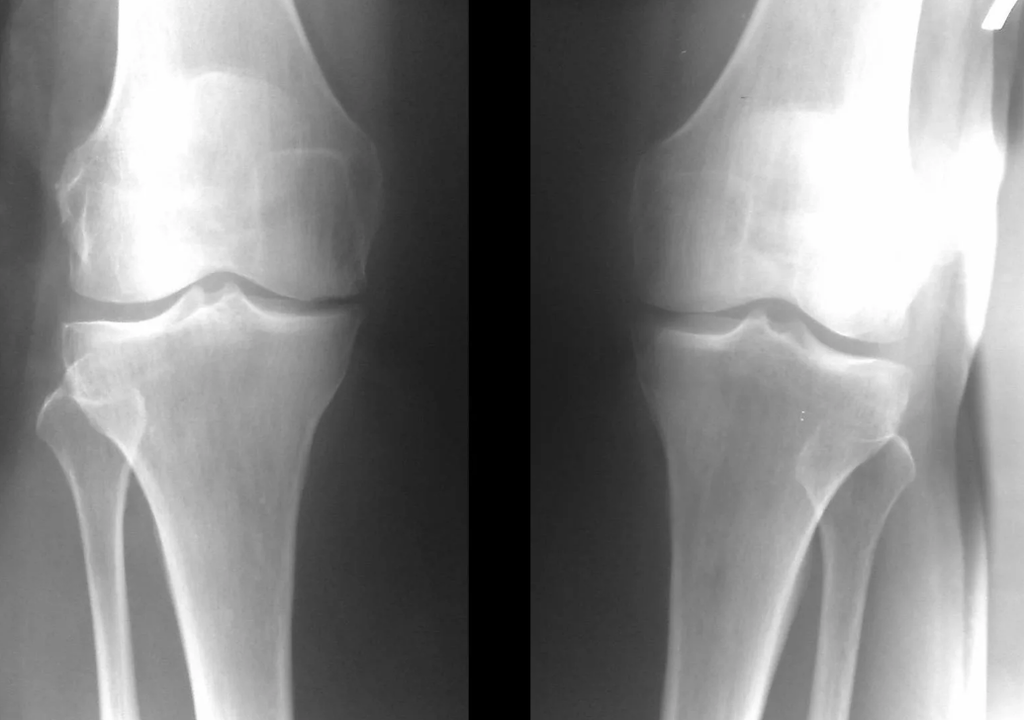

Instrumental diagnosis of arthrosis of the knee joint

In most cases, examination and x-ray of the knee joint in two projections (direct and lateral) is sufficient.Clinical data and images help determine the stage of the disease.

In the early stages of the disease, with minor changes in bone tissue, X-ray examination is not very valuable.At this stage, gonarthrosis can be diagnosed through arthroscopy.The accuracy of the method is very high;only its invasive nature and price can prevent it.

In the second stage, the cartilage layer becomes thinner, and in some places is completely absent.Osteophytes appear along the edges of the articular surface.The qualitative and quantitative characteristics of the synovial fluid of the joint changes - it becomes thicker, more viscous, which leads to a deterioration in its nutritional and lubricating properties.The pain is more prolonged and intense, and a throbbing sound often appears when moving.There is little or moderate movement restriction and little joint deformity.Taking analgesics helps relieve pain.

Lack of cartilage in the most affected areas, severe sclerosis (hardening) of the bones, many osteophytes and sharp narrowing or absence of the joint space.The pain is almost constant, the gait is disturbed.Mobility is very limited, and joint deformation can be seen.NSAIDs, physiotherapy and other standard methods of treating knee arthrosis are ineffective.